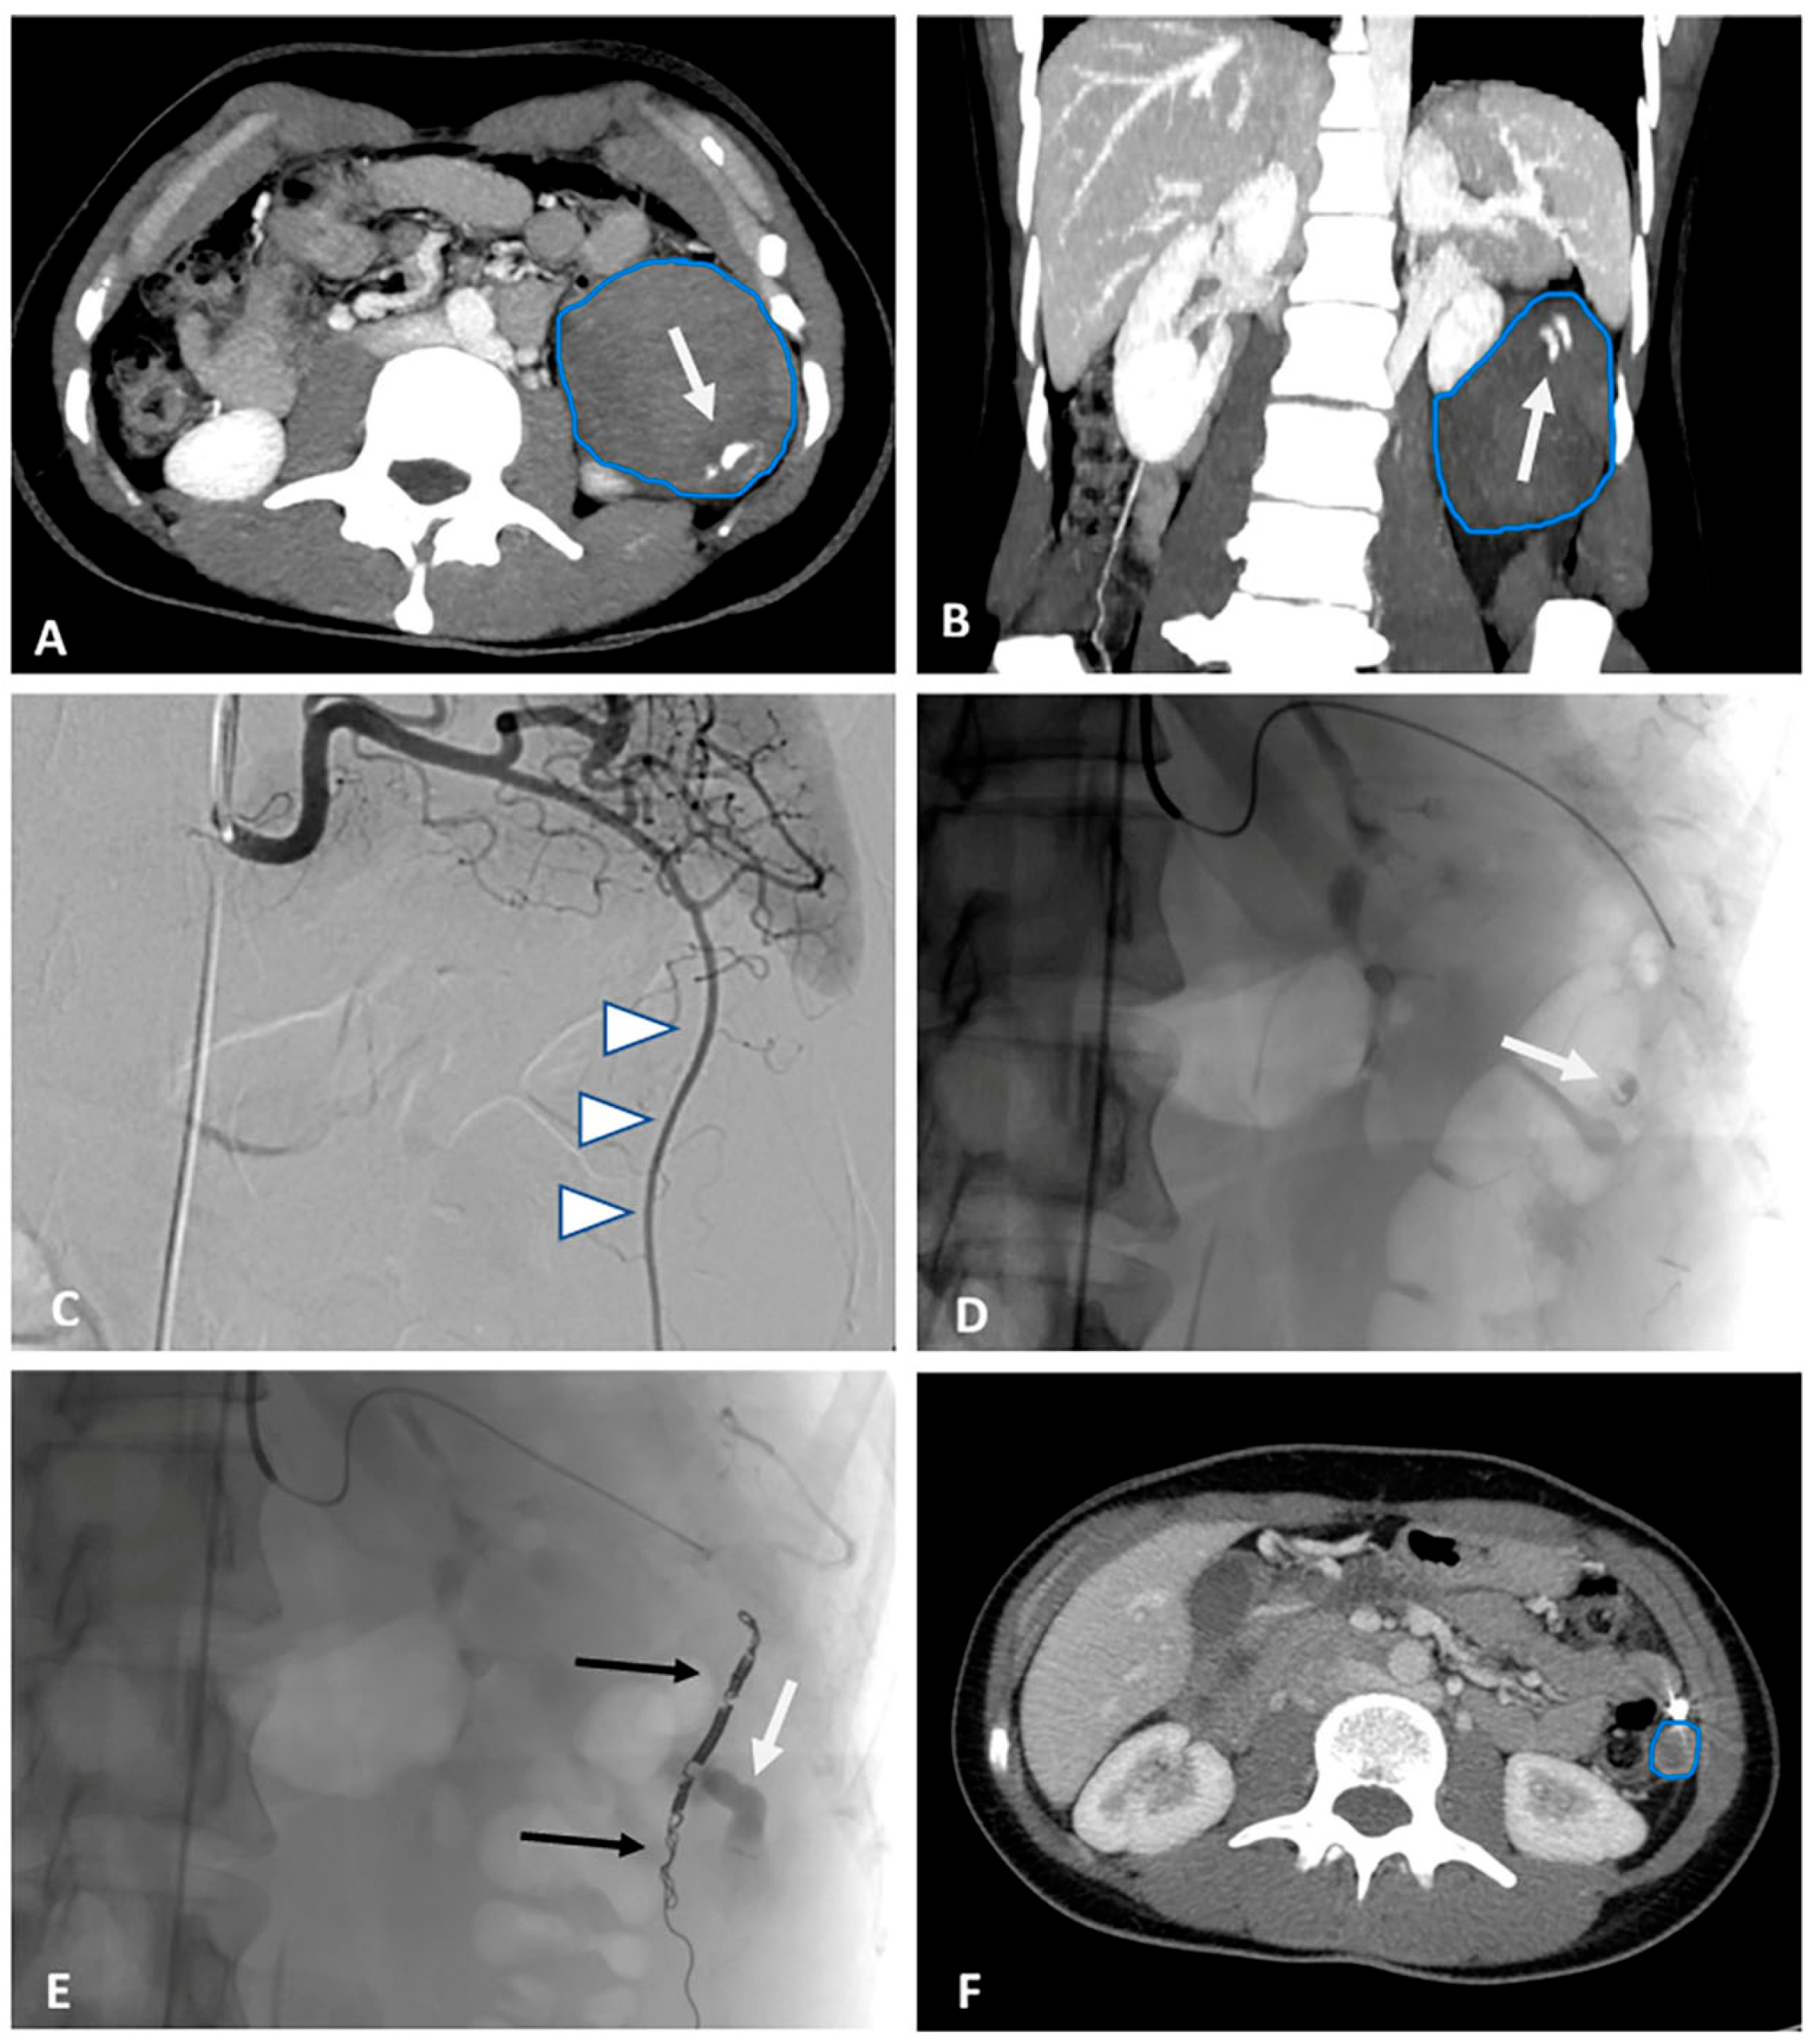

A computed tomography (CT) scan was performed to differentiate the mass found on ultrasound. Abdominal and pelvic CT showed a 68 × 60 × 87 mm heterogenic mass, likely a hematoma, which was below the spleen. Pelvis was filled with hemorrhagic fluid, and the uterus was enlarged. Arterial extravasation was spotted from the lower spleen pole. Conventional angiography of the splenic artery was performed, and extravasation was identified in the region below the spleen. The vessel was embolized (Figure 1A–E). Due to the unknown origin of the hematoma and the recent history of surgery for ectopic pregnancy, and gynecologist consultation was sought. The gynecologist ordered a urine pregnancy test, which was positive. The serum human chorionic gonadotropin (hCG) concentration was 3363.6 U/L. The clinical case was considered a rare pathology of extratubal secondary trophoblastic tissue reimplantation. As the bleeding was stopped with embolization, a conservative two-dose methotrexate (MTX) treatment protocol with MTX 50 mg per square meter of body surface area intramuscularly (mg/m2 BSA i/m) on day 1 and day 4 was administered. Abdominal pain did not intensify; subjectively, the woman started feeling better. The decrease in serum hCG concentration between days 4 and 7 was 24.1% (i.e., more than 15%); thus, hCG testing was repeated weekly (Chart 1). Menstruation renewed 29 days after the first dose of MTX. Seven months later, the CT scan showed that the size of the heterogenic mass below the spleen decreased to 18 × 14 × 16 mm (Figure 1F).

Figure 1. Axial and coronal 15 mm maximum intensity projections (contrast-enhanced computed tomography (CE-CT) in the emergency department, prior to embolization), large hematoma is seen in the upper left abdomen (blue outline) with active arterial extravasation (white arrow) (A,B). Digital subtraction angiography of coeliac trunk shows unusual large arterial branch (white arrowheads) descending from the splenic artery to lower abdomen—most likely hypertrophied left epiploic artery (C). Selective angiography with micro catheter shows slow arterial extravasation (white arrow) (D). Post-embolization image (E) with embolizing coils (black arrows) above and below extravasation site, also stagnated contrast medium in hematoma can be seen (white arrow). Significant size reduction of hematoma is seen at 7 month follow-up CT image (blue outline) (F).